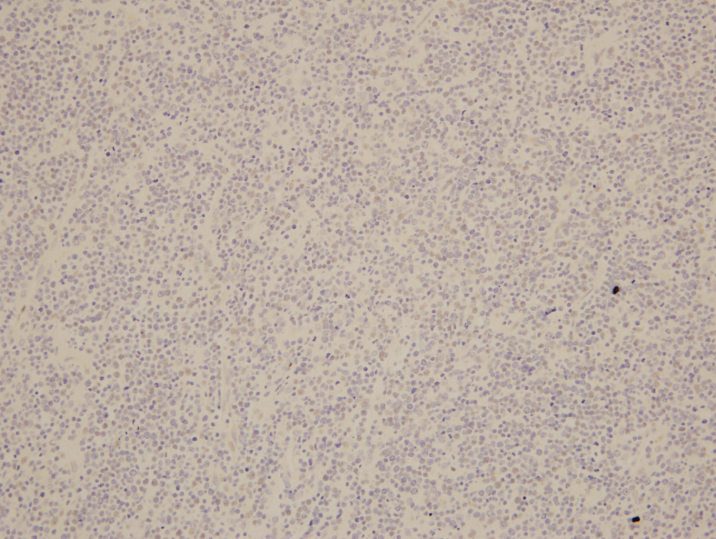

The McLeod phenotype is frequently associated with CGD due to the proximity of the XK gene to the CYBB gene on the X chromosome. The CYBB gene encodes for a subunit of the NADPH oxidase enzyme complex. A deficiency in NADPH oxidase activity leads to the characteristic increased susceptibility to severe bacterial and fungal infections seen in CGD. The nitroblue-tetrazolium test can be used to evaluate NADPH oxidase activity in the white blood cells and can help make a diagnosis of CGD. Histologically, CGD can show prominent necrotizing and non-necrotizing granulomas in various locations throughout the body.